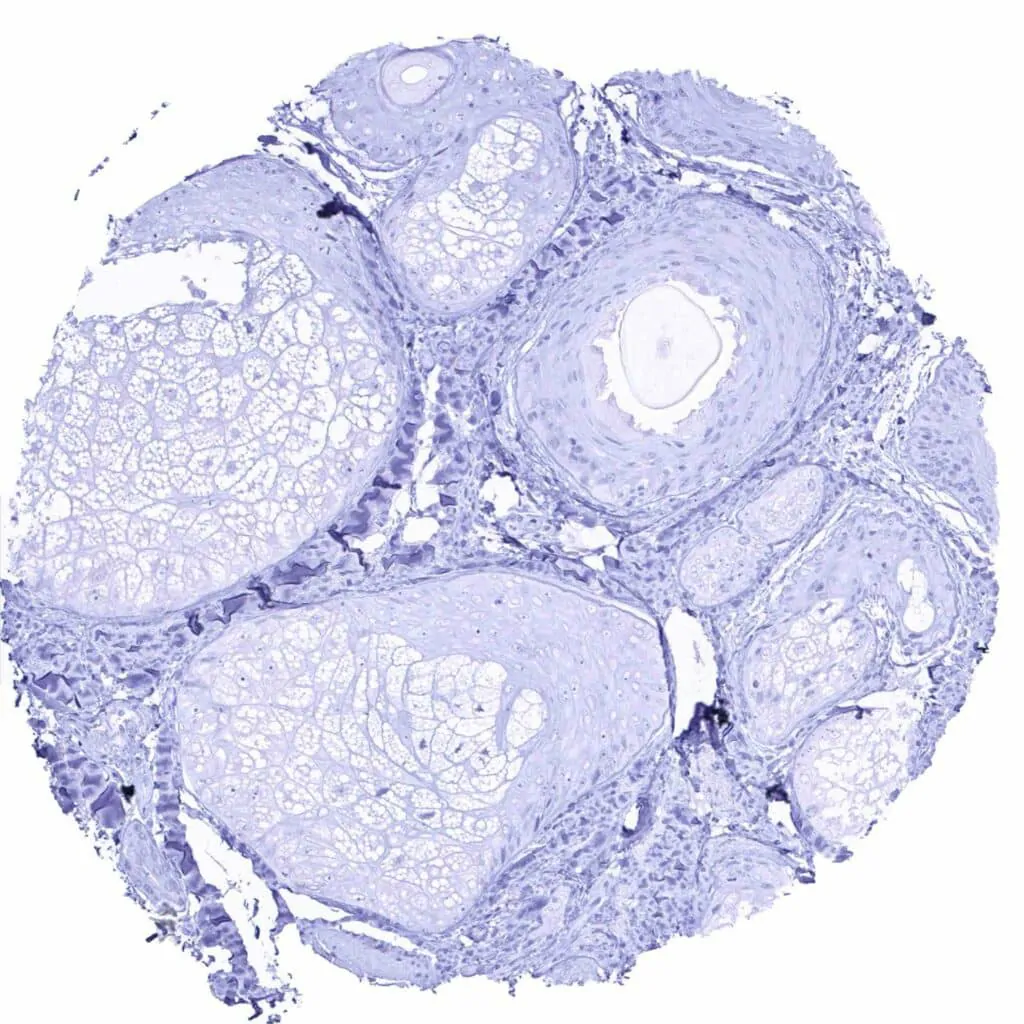

Testis